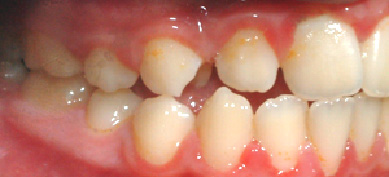

2) Οι φωτογραφίες του ασθενούς

Από τη μελέτη αυτών θα προκύψει εάν υπάρχει ορθοδοντικό πρόβλημα το οποίο μπορεί να εντοπίζεται μόνο στα δόντια ( συνωστισμός, στροφές, έκτοπη εντόπιση), είτε να υπάρχει και σκελετικό πρόβλημα ( στενή γνάθος, προγναθισμός ή οπισθογναθισμός, ασσυμετρίες, σκελετική υπερσύγκλειση ή ανοικτή δήξη).